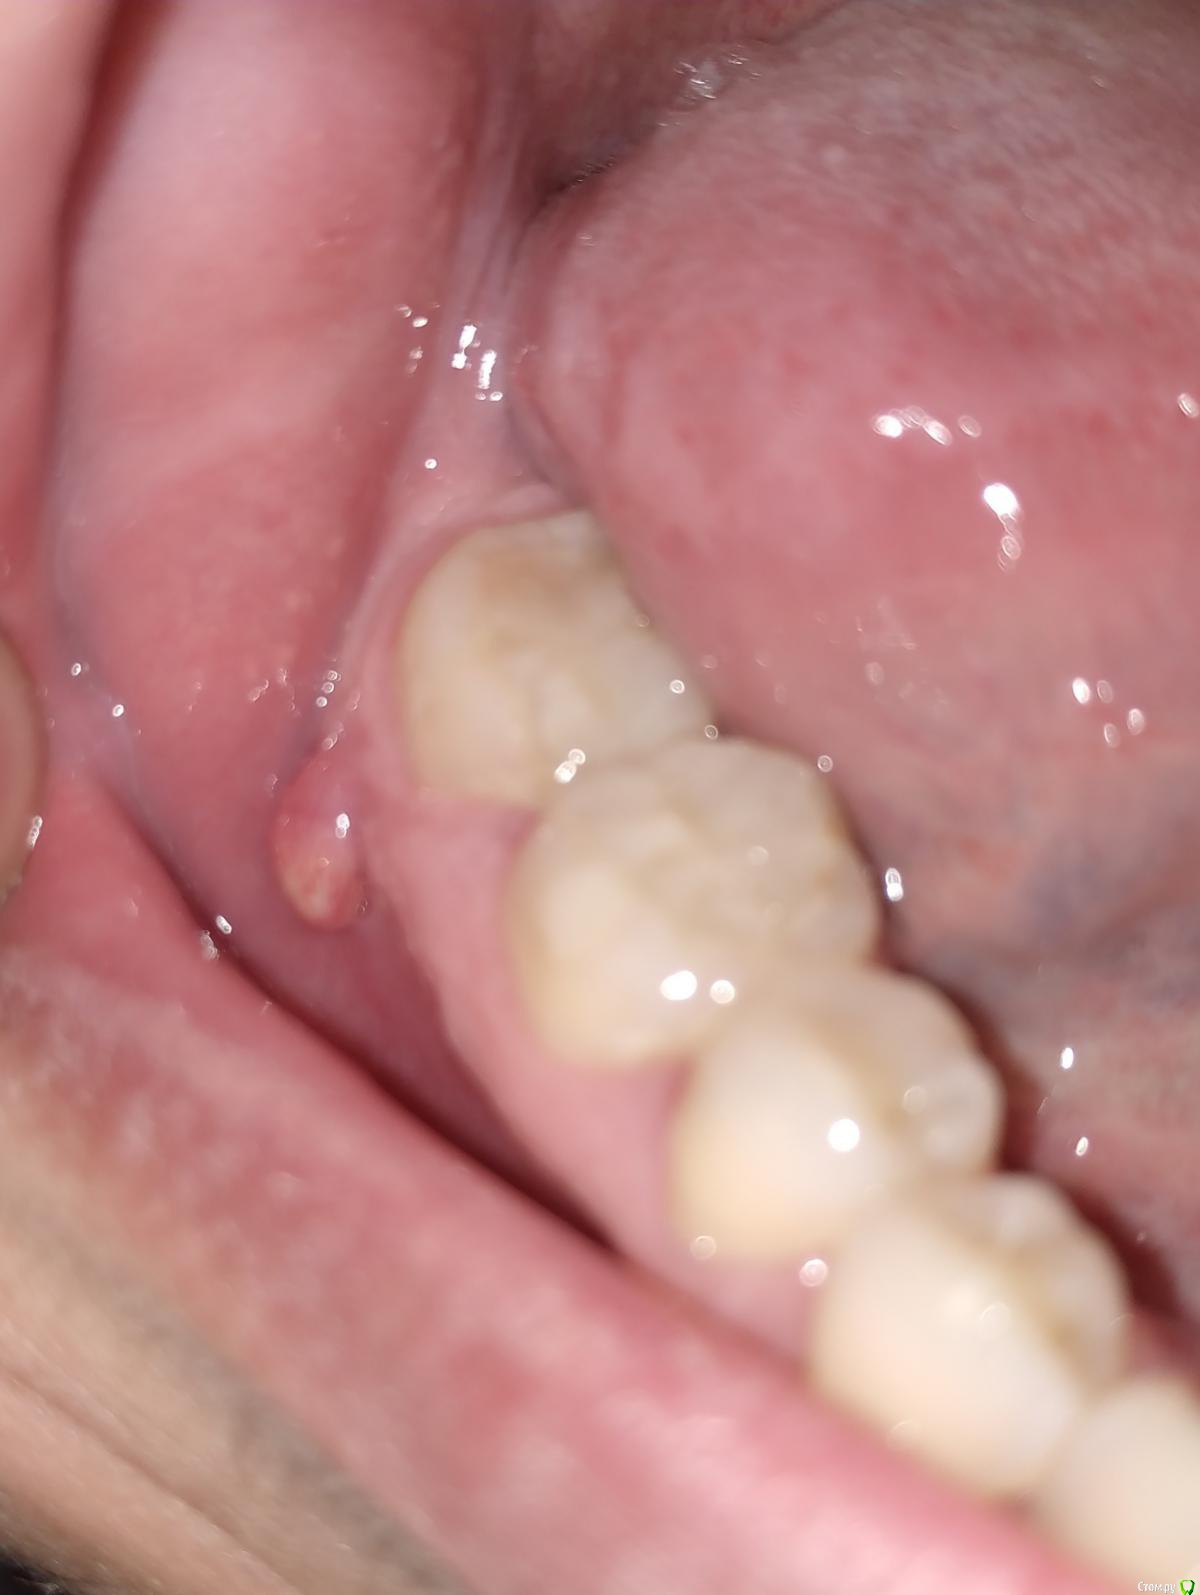

Vlad7772 Опубликовано 6 августа, 2019 Поделиться Опубликовано 6 августа, 2019 Добрый вечер, подскажите пожалуйста, что это может быть и что с этим делать, дня 4 назад появился такой нарост на десне, обнаружил случайно, дискомфорта нет, не болит, по ощущениям мягкий.Заранее, спасибо. Ссылка на комментарий

red_butler Опубликовано 6 августа, 2019 Поделиться Опубликовано 6 августа, 2019 Похоже на свищ, сделайте Rg зуба Ссылка на комментарий

Saymon Опубликовано 6 августа, 2019 Поделиться Опубликовано 6 августа, 2019 (изменено) Лучше всего записаться к эндодонтисту на приём и сделать компьютерную томографию. Предположительно на последнем зубе воспалительный процесс, что в свою очередь спровоцировало образование свища. Изменено 6 августа, 2019 пользователем Saymon Ссылка на комментарий